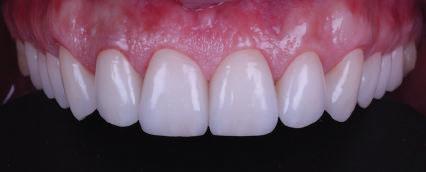

КРАТКО ОПИСАНИЕ

Пациентът постъпи в клиниката с молба за тотална рехабилитация на усмивката. Той не харесваше централ ните си резци, които според него бяха твърде къси и квадратни. Имаше раз стояние от медиално и дистално на латералните му резци. Друго сериоз но оплакване бе свързано с металоке рамичната корона на зъб 12, която бе жълтеникава и неестетична, като цяло не харесваше вида на венците си и както самият той се изразяваше, „вижда се прекалено много от венците при усмивка“.

ЛЕЧЕБНИЯТ ПЛАН ПРИ ТОЗИ СЛУЧАЙ БЕШЕ СЛЕДНИЯТ: Диагностика, фотодокументация,

След диагностиката бяха направени екстра- и интраорални снимки, както и рентгенографии; професионалното почистване бе от изключителна важ ност, бяха дадени и инструкции за лич на орална хигиена. Бе направено интра орално сканиране с Medit i500. Цялата тази информация бе използ вана в приложението Smilecloud за 2D биометричен дизайн. В приложението са налични естест вени форми на зъбите и щом бяха под брани зъби и бе направен дизайн

библиотеката на Exocad. Струва си да се отбележи, че 2D дизайнът от Smile Cloud бе спазен до последния детайл в Exocad smile creator с цел да се създаде 3D obj файл със зъбните форми. След като естетичният дизайн бе готов в model creator модула на Exocad, адитивен 3D мок-ъп модел бе експорти ран и принтиран от принтер Formlabs 3. Моделът бе използван за направата на силиконов водач, за да се изготви мо тивационен мок-ъп в устата на паци ента и да се оценят естетичните па раметри. След като пациентът одобри вида на усмивката си, мок-ъпът бе използван за финализиране дизайна на усмивка та. Мок-ъпът бе използван също така като водач по време на мекотъканна та хирургия, както и при препарация на зъбите.

Препарираните зъби бяха импорти рани в Exocad и насложени върху ес тествените форми от биометричния дизайн, като така стана ясно дали зъ бите са били препарирани коректно. По този начин зъболекарят и зъботехни кът работят в една и съща екосистема и резултатът е оптимален. С короната се справихме чрез диги тална редукция на циркония в Exocad, като по този начин на практика създа дохме циркониево кепе, след което про изведохме фасета от IPS Empress Cad Multi. Кепето от Katana Zirconia на зъб 12 с букално послойно нанесена керами ка бе фрезовано (послойното нанасяне бе направено, за да се подобри връзката и да се осигури адхезивно циментиране на фасетата към циркониевото кепе, както и за да се напасне цветът към този на съседните зъби). При първото сканиране регистрирах ме цялата горна зъбна дъга, така че, ко гато се наложи да сканираме повторно, бе изтрит и сканиран наново само зъб 12, тъй като венците не бяха отдръп нати при второто сканиране.

рентгенографии. Инициална терапия и професионално почистване. Интраорално сканиране с цел диги тално планиране. Регистрация и 3D ориентиране на ок лузалната равнина на горна и долна челюст в пространството. 2D дигитално планиране и дизайн на усмивката посредством приложение то Smile Cloud. 3D дигитално планиране и дизайн на функционалните и естетичните па раметри. 3D дигитален дизайн и адитивен мокъп на горна челюст. 3D принтиране и мок-ъп модели. Мотивационен мок-ъп. Фини корекции за постигане на фи налния дизайн. Мекотъканна хирургия с мок-ъпа като водач Препарация през мок-ъпа, използвай ки дизайна като водач за финалната препарация в Exocad. Циркониево кепе ще бъде циментира но с цел адхезивно залепяне на фасе та на края. Кепето има същия цвят като този на съседните зъби, за да може фасетата да се впише перфект но в цялостната усмивка. Изработване на 12 IPS Empress Cad Multi фасети с послойно нанесена ке ТОТАЛНА РЕХАБИЛИТАЦИЯ НА УСМИВКАТА С ИЗЦЯЛО ДИГИТАЛЕН ПРОТОКОЛ Д-р Калин Маринов и зт. Стефан Петров рамика букално върху зъбните препа рации и върху първичното циркони ево кепе (има възможност за ецване и адхезивно

Една седмица след препарацията на зъбите и циментирането на цирко ниевото кепе бяха изработени 12 IPS Empress Cad Multi фасети. Макро- и микротекстурата на фасе тите бяха направени на ръка, след кое то бяха нанесени 3D характеризации с боички, а полирането отново бе напра вено ръчно, за да им се придаде естест вен и естетичен вид. Предизвикателството тук беше короната да има същите оптични характеристики като тези на остана лите зъби при естествена светлина, през поляризационен и флуоресцентен филтър. 3D принтерът бе Fromlabs, софтуерът за фрезоване – Mill Box, а фрез апаратът –imes icore CORiTEC 350i. В крайна сметка постигнахме ес тествен вид на усмивката с натурал на зъбна морфология при изцяло диги тален протокол, при който дизайнът бе направен първоначално и през всич ки етапи на лечението се придържахме към него до самия край Излишно е да отбелязваме, че всички сме удовлетворени от постигнатото! Преди След Победител в категория „Клиничен случай с изцяло дигитален протокол“ в конкурса „Усмивка на годината 2022“

11Dental Tribune Bulgarian Edition / октомври 2022 г. Преди лечението Фиг. 1 Фиг. 2 Фиг. 3 Фиг. 4 Фиг. 5 Фиг. 6 Фиг. 7 Фиг. 9 Фиг. 10 Фиг. 11 Фиг. 8 Фиг. 12 Фиг. 13

12 Dental Tribune Bulgarian Edition / октомври 2022 г. По време на лечението Фиг. 14 Фиг. 16 Фиг. 20 Фиг. 23 Фиг. 21 Фиг. 24 Фиг. 26 Фиг. 28 Фиг. 31 Фиг. 34 Фиг. 29 Фиг. 32 Фиг. 35 Фиг. 30 Фиг. 33 Фиг. 36 Фиг. 27 Фиг. 22 Фиг. 25 Фиг. 17 Фиг. 18 Фиг. 19 Фиг. 15

13Dental Tribune Bulgarian Edition / октомври 2022 г. След лечението За авторите: Д-р Калин Маринов е специалист в областта на имплантологията, протетиката и естетичната хирургия. Завършил е дентална медици на в София през 2012 г. През 2014 г. основава Sky Dental Clinic. Бил е на обмен ни начала в катедра „Протетика“ на Университета по дентална медицина във Фрайбург, Германия. Живял е и е практикувал в Мелбърн, Австралия, и е посеща вал курсове и лекции в Италия, Швейцария, Германия с насоченост в естетич ната хирургия и имплантология, както и тоталната рехабилитация на устна та кухина чрез импланти. Зт. Стефан Петров основава собствена лаборатория през 2006 г. Официален демонстратор на GC за България, като от 2015 г. е KOL за Източна Европа. Инструктор е на Straumann за България. Лаборатория та му има сертификат за пилотна лаборатория на Micerium – Италия. Носител е на множество награди в денталния конкурс „Усмивка на годината”. Носител е на награда CERAMISTS MASTER CUP с д-р Софиен Риахи в престижния международен конгрес CERAMISTS – NO LIMITS 2015 г. Изнася лекции и провежда курсове в редица европейски страни. Фиг. 37 Фиг. 40 Фиг. 43 Фиг. 45 Фиг. 47 Фиг. 50 Фиг. 48 Фиг. 49 Фиг. 41 Фиг. 44 Фиг. 46 Фиг. 42 Фиг. 38 Фиг. 39